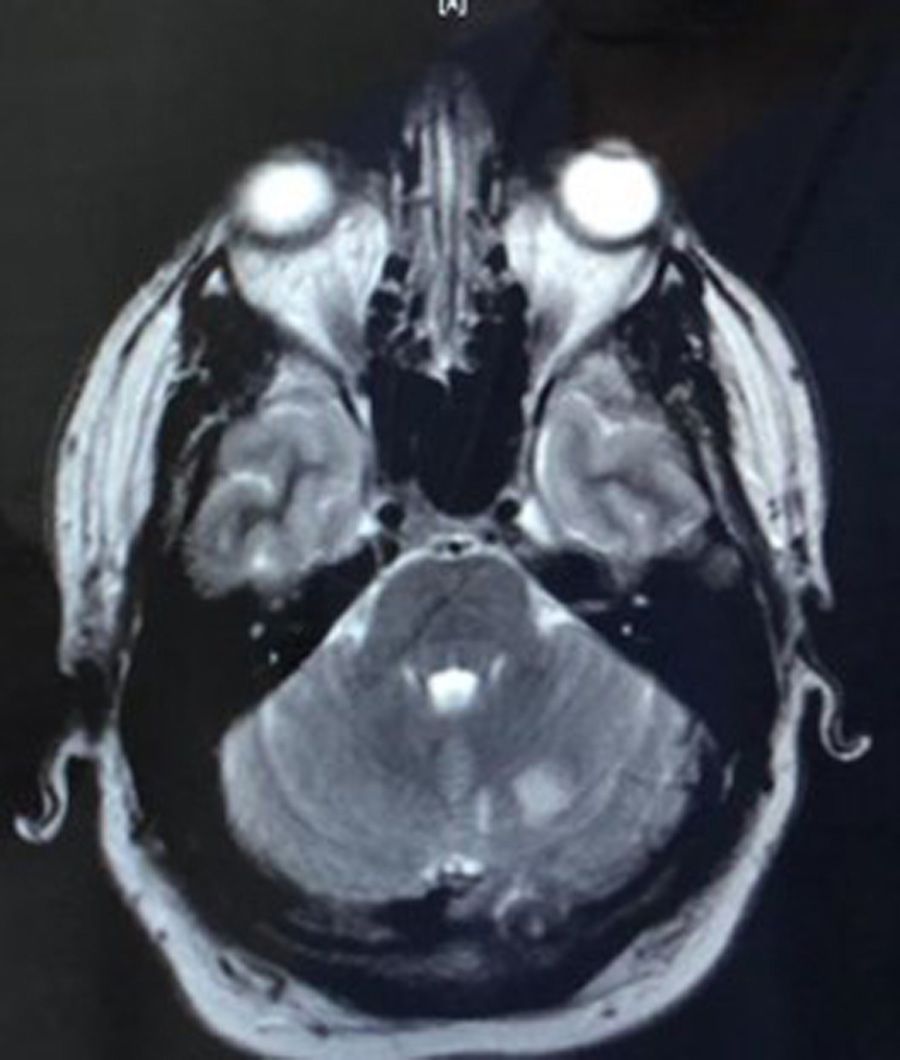

“I was admitted to Arrowe Park Hospital on the Wirral where they did a CT scan and MRI scan which showed two areas of damage to my brain and confirmed I'd had a stroke."

“Although I had not had another stroke, an MRA scan, which looks inside the blood vessels, showed that I had a dissection of the cerebral artery and I was referred to the Walton Centre for Neurology and Neurosurgery in Liverpool, which is managing my on-going care."

“I'm under the care of the Walton Centre having on going engagement with my neurologist. They monitor the dissection via MRI scans and will decide on a course of treatment."